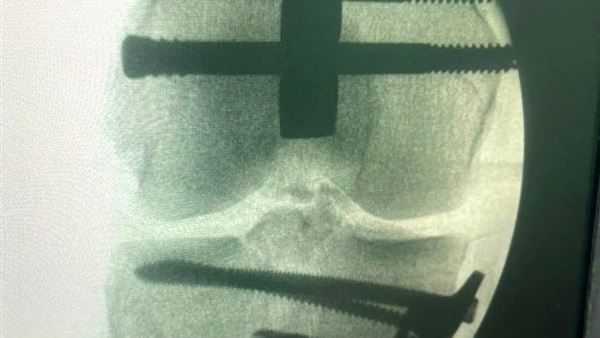

وبعد استقرار المؤشرات الحيوية، جرى نقله على الفور إلى قسم العظام، حيث كشفت الفحوصات عن إصابات بالغة ومتعددة، تمثلت في كسر مضاعف بالساق اليمنى، وكسر بمفصل الركبة اليمنى، وكسر بالفخذ الأيمن، بالإضافة إلى تهتك شديد وفقدان جزء من جلد القدم.

وعلى الفور، وضع الفريق الطبي خطة علاجية دقيقة للتدخل الجراحي العاجل، حيث أجرى أطباء العظام عملية معقدة نجحوا خلالها في تثبيت الكسور باستخدام الشرائح والمسامير والمسامير النخاعية بكفاءة عالية، ما أسهم في إنقاذ الساق المصابة واستقرار الحالة بشكل كبير، لتبدأ بعدها مرحلة جديدة من التعافي والرعاية المكثفة.